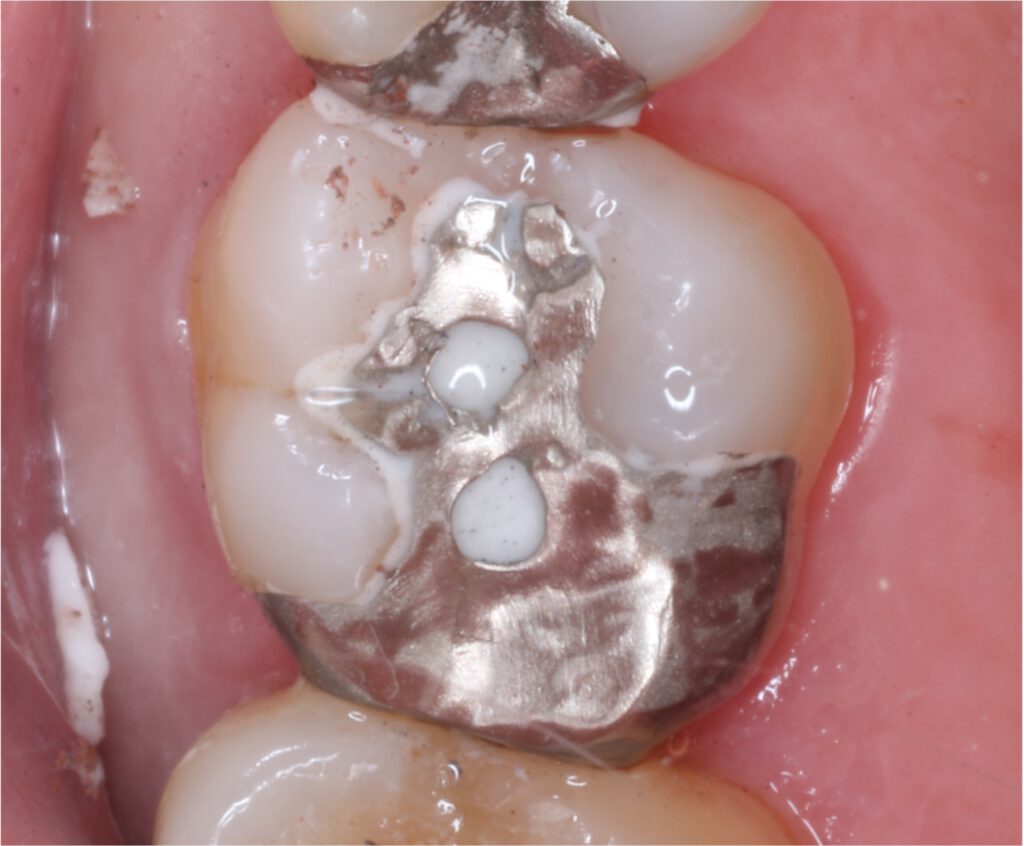

01精密根管治療

「抜くしかない」と言われた歯でも、根の中の感染を適切に抑えられる治療技術があれば、歯を残せる可能性があります。根管は非常に細く複雑で、わずかな取り残しが痛みや腫れの再発につながることもあるため、当院では必要に応じてCTやマイクロスコープを活用し、原因を見極めながら丁寧に処置を進めます。

医療法人大杉歯科医院が大切にしているのは、早く終える治療ではなく、歯を守る治療。津市で、できるだけ天然歯を残したい方の選択肢になれるよう取り組んでいます。症例1

- 治療名

- マイクロスコープとラバーダムを使用した精密根管治療

- 患者様

- 30代男性

- 執刀医

- Dr. 大杉

- 治療期間

- 3ヶ月

- 治療費

- 精密根管治療:130,000円(税込)

築造:40,000円(税込) - リスク

- 治療中〜治療後に痛みが出る場合あり

再感染・治癒不全の可能性

補綴後も定期管理が必要

症例2

- 40代女性

築造:40,000円(税込)

セラミック:130,000円(税込) - リスク